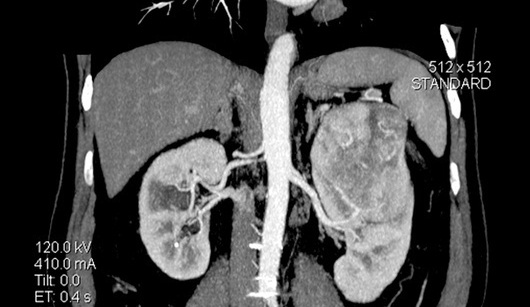

КТ картина

опухоли левой почки >>>